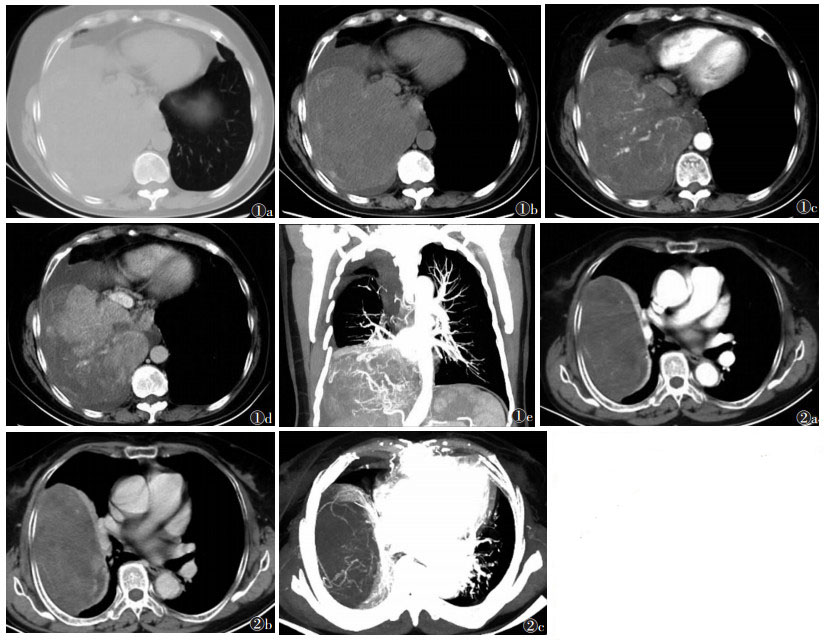

2.2 CT表现10例中7例行CT平扫,2例密度不均;2例伴低密度区,边缘CT值42~71 HU,平均(56.5±20.5)HU,中央CT值21~30 HU,平均(25.5±6.36)HU;其余3例呈软组织密度肿块,CT值35~61 HU,平均(42.0±10.5)HU。10例行CT增强扫描,4例较大病灶(直径>10 cm)不均匀强化,其内可见血管影,呈“肿瘤包绕血管征”,即肿块内有穿行的血管影(图 1),其中2例伴低密度区及边缘强化区(图 2),低密度区轻度强化,动脉期CT值11~40 HU,平均(22.3±15.5)HU,静脉期CT值7~48 HU,平均(25.3±20.8)HU;边缘明显强化,CT值103 HU。其余6例较小病灶(直径 < 5 cm)表现为均匀强化,动脉期CT值38~70 HU,平均(54.5±14.6)HU,静脉期CT值63~80 HU,平均(68.0±8.12)HU。3例伴胸腔积液(图 1)。

| 图 1 女,55岁,因间断胸闷、胸痛半年,伴咳嗽15 d入院 图 1a,1b CT平扫肺窗及纵隔窗示右侧胸腔一巨大实性占位性病变,与胸膜呈宽基底相连,边界较清,伴右侧胸腔积液 图 1c,1d 分别为增强扫描动脉期及静脉期示肿块内部不均匀强化,其内见血管影 图 1e MIP冠状位示肿块邻近纵隔及胸椎,体积巨大,呈“肿瘤包绕血管征”,压迫邻近肺组织造成局部肺不张 图 2 男,61岁,因咳嗽伴左侧胸痛1周入院 图 2a,2b 分别为增强扫描动脉期及静脉期示病灶横跨右肺上叶及中叶,边界清晰,肿块内部强化欠均匀,边缘明显强化,其内伴少许小片状低密度影,未见明显强化 图 2c MIP轴位可见较大肿块内见穿行血管影,呈典型“肿瘤包绕血管征” |